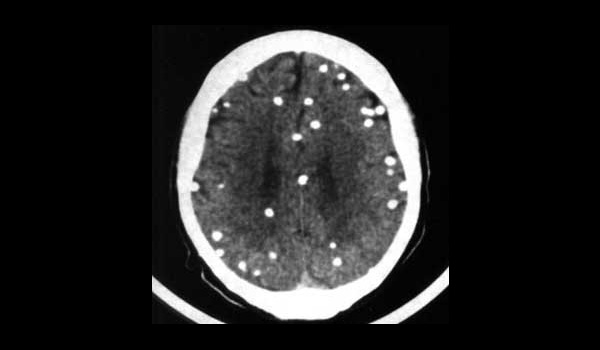

TAC cráneo simple: Neurocisticercosis intraparenquimatosa calcificada.